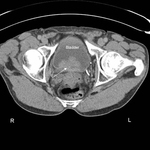

CT scan showing transitional cell carcinoma of the bladder blocking the right ureteric orifice

From the personal collection of Dr Kasra Saeb-Parsy